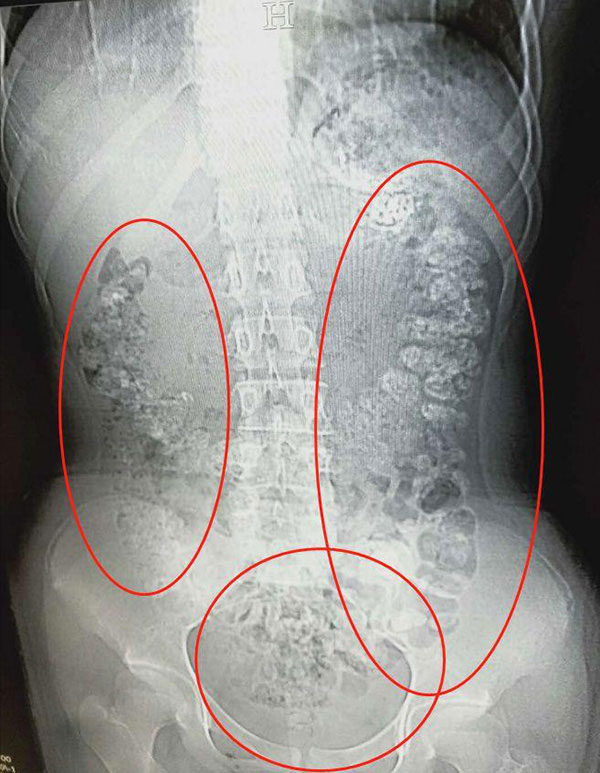

14岁女孩喝了珍珠奶茶后,五天没有排便,还肚子疼,CT检查发现胃肠道布满一颗颗圆圆的高密度阴影——没有消化的“珍珠”。

5月28日晚,女孩小沈(化名)在父母陪同下到浙江诸暨市人民医院急诊,说肚子疼,几天无法排便,也吃不下东西。接诊医生张楼炜见她肚子鼓鼓的,便安排了腹部CT,检查结果让他一惊:患者胃部、横结肠、升结肠、降结肠、乙状结肠,一直到肛门,全是颗粒状阴影,足有百余颗。